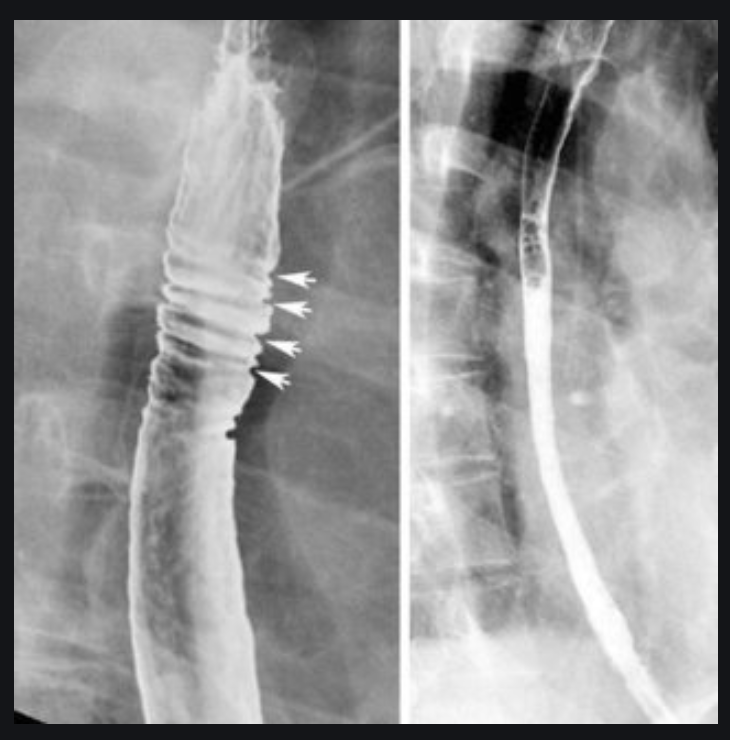

WHAT IS THIS?

histopathology

- Oesophagus is abnormally lined with columnar, metaplastic acid-secreting gastric mucosa.

- It is usually due to chronic reflux oesophagitis.

- Because there is an increased risk of oesophageal cancer, close follow-up and repeated biopsies are recommended

- IMAGING FEATURES

- A reticular mucosal pattern which may be discontinuous in the distal oesophagus (short segment) is the most sensitive finding.

- Suspect diagnosis if there is

- upper or midoesophageal stricture accompanied by reticular mucosal pattern below transition or ulcer

- Low strictures:

- the majority cannot be differentiated from simple reflux oesophagitis strictures and biopsies are required.

https://radiopaedia.org/cases/barrett-oesophagus?lang=gb

Zoomed-in images of the fine reticular pattern superimposed on oesophagitis (fine granular pattern) found in Barrett oesophagus. The area of fine reticulation is either circled in red or pointed to with red arrows.

Thanks to Steve Rubesin MD for this case.

Case Discussion

Biopsy proven Barrett oesophagus (no histologic dysplasia). This is more than an incidental finding on an oesophagram – this is a critical finding. By the time you find a lobulated oesophageal carcinoma it’s too late; the patient needs to be treated and followed at the first signs of metaplasia in the normal oesophageal stratified squamous epithelium.

It is important to get enough air/gas in the oesophagus in order to optimise one’s double contrast technique and pick up subtle findings like this. In addition to effervescent granules, it is often helpful to tell the patient to swallow as much air as possible while drinking the barium.

In this example, the Barrett oesophagus is at the gastro-oesophageal junction, but it can occur in patches anywhere from the mid-oesophagus down to the gastro-oesophageal junction.